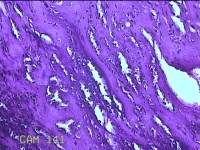

胎盘组织

性别

女

年龄

31岁

临床诊断

提前自然临产伴有足月产

一般病史

停经39+1周。

标本名称

大体所见

灰白暗红色胎盘组织19x15x2.3㎝一个,表面光滑,血管清晰,颜色发暗,绒毛面结节状,轻度糜烂,表面有少许凝血块,切面见绒毛内有部分淤血,边缘蜕膜可见多个小血肿,脐带49x1.3x0.8㎝,切断脐带,见脐血管内有凝血块。

图1